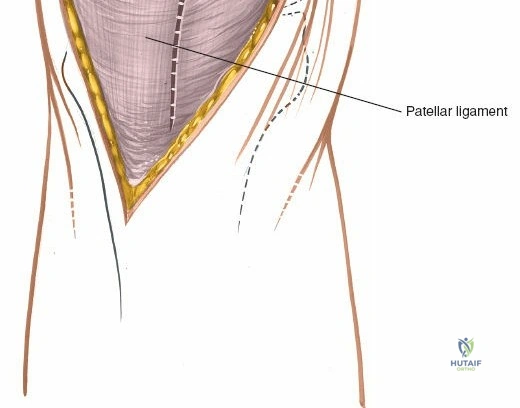

The extensor mechanism comprises the quadriceps femoris muscle group, the quadriceps tendon, the patella, the patellar tendon (ligament), and its insertion into the tibial tubercle.

* Patellar Tendon: Connects the patella to the tibial tubercle.

The medial retinaculum and vastus medialis obliquus are exposed. The proposed capsular incision along the medial patellar border is outlined.